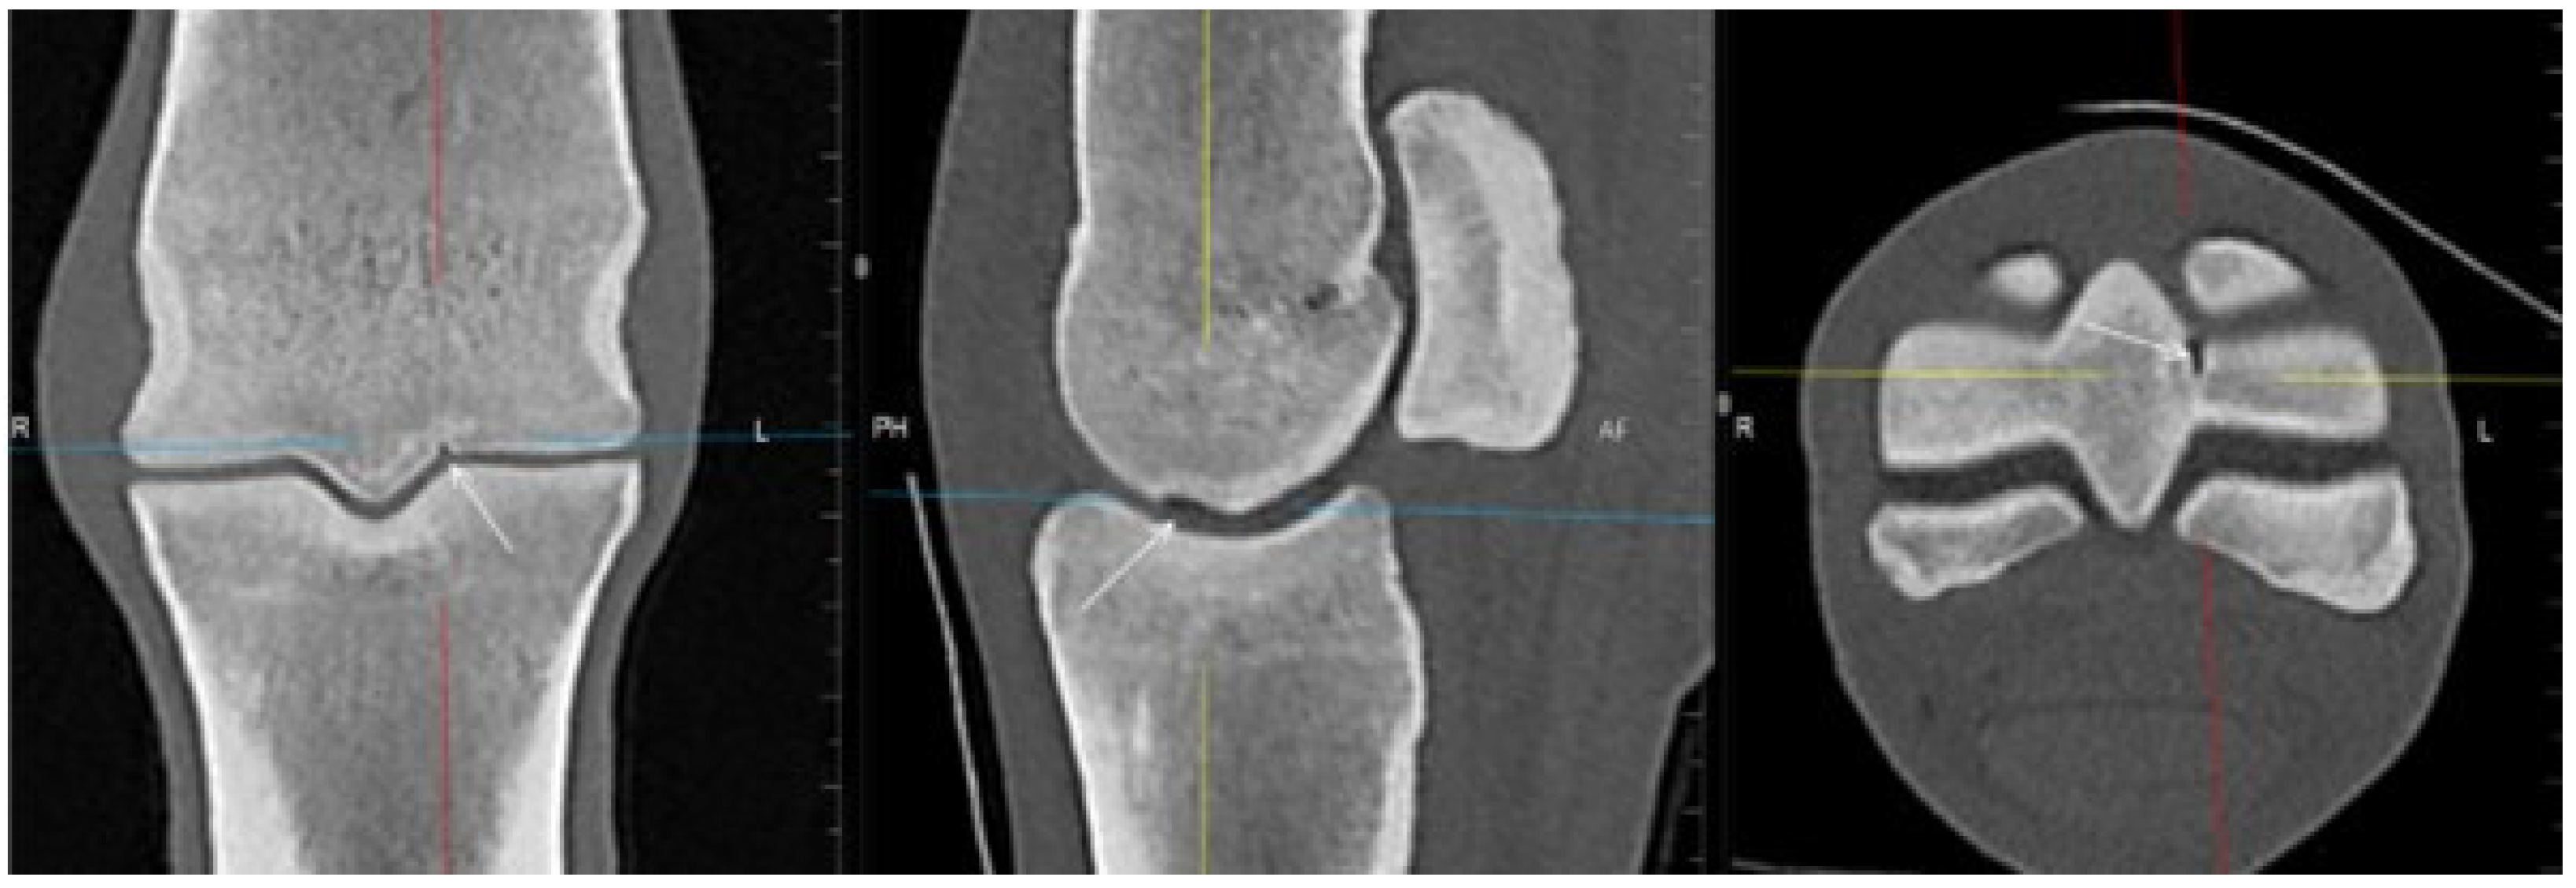

3.1. The Third Metacarpal Bone (McIII)

3.2. The Proximal Phalanx

| Hypoattenuating lesion in the dorsal subchondral bone Subchondral bone thickening Dorsal/palmar half Increased attenuation in the trabecular bone Dorsal/palmar half Cone shaped/patchy Focal separated hyperattenuation | Hyperintense signal in the dorsal subchondral bone Subchondral bone thickening Dorsal/palmar half Decreased signal intensity in the trabecular bone Dorsal/palmar half Cone shaped/patchy Focal separated intermediate/low signal intensity | Radiolucent lesion Subchondral bone thickening Dorsal Increased trabecular bone opacity | |

| Subchondral bone thickening Dorsal/palmar half Increased attenuation in the trabecular bone Dorsal/palmar half Hypoattenuating lesion in the subchondral bone Location | Subchondral bone thickening Dorsal/palmar half Decreased signal intensity in the trabecular bone Dorsal/palmar half Increased signal intensity in the subchondral bone Location | Increased opacity in the trabecular bone Lucent lesion in the subchondral bone Location | |

| Proximal phalanx Sagittal groove | |||

| Subchondral bone thickening Dorsal/middle/palmar third Increased attenuation in the trabecular bone Hypoattenuating lesion in the subchondral bone Location | Subchondral bone thickening Dorsal/middle/palmar third Decreased signal intensity in the trabecular bone Increased signal intensity in the subchondral bone Location | Subchondral bone thickening Increased opacity in the trabecular bone Lucent lesion in the subchondral bone Location | |